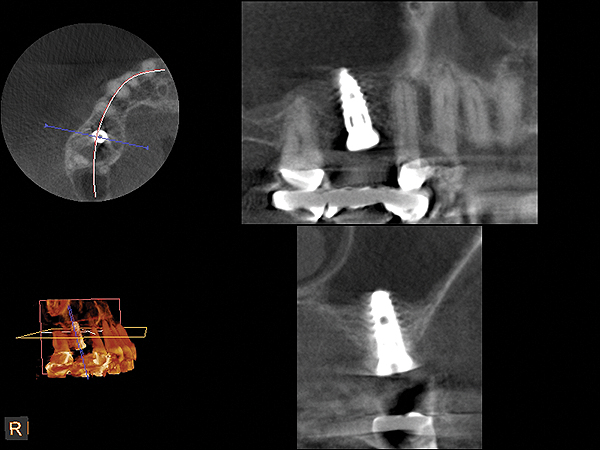

A 74-year-old male patient presented with about 4 mm to 5 mm of native bone in the No. 4 position (Figure 17). A composite graft, as described in Case 1, was used, as was the same implant type, but the implant was 11.5 mm in length with a taper of 5 mm to 4.2 mm. The approximately 16-month post-healed floor of the sinus was raised about 7 mm to 8 mm (Figure 18). The CBCT scan taken at 16 months postoperatively showed no change in appearance from the area of the old floor of the sinus to the new bone formed (Figure 19). Although it was endodontically involved, tooth No. 15 was not extracted, against professional advice. As can be seen in Figure 18, the No. 14 implant is acting as a bridge abutment.

Fig 19. CBCT scan (Kodak 9000D) of implant No. 14 showing homogeneous appearance of the bone.

Figure 19